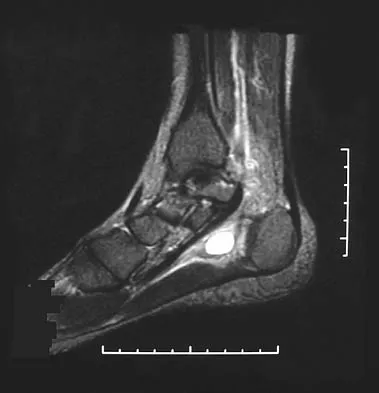

An 8-year-old boy with severe hemophilia A (factor VIII) and no inhibitor is averaging eight transfusions per month for bleeding into the right ankle. Examination shows synovial hypertrophy; range of motion consists of 0 degrees of dorsiflexion and 20 degrees of plantar flexion. The patient's knees, elbows, and left ankle have no restriction of motion. Standing radiographs of the right ankle are shown in Figure 18. Management should consist of

Explanation